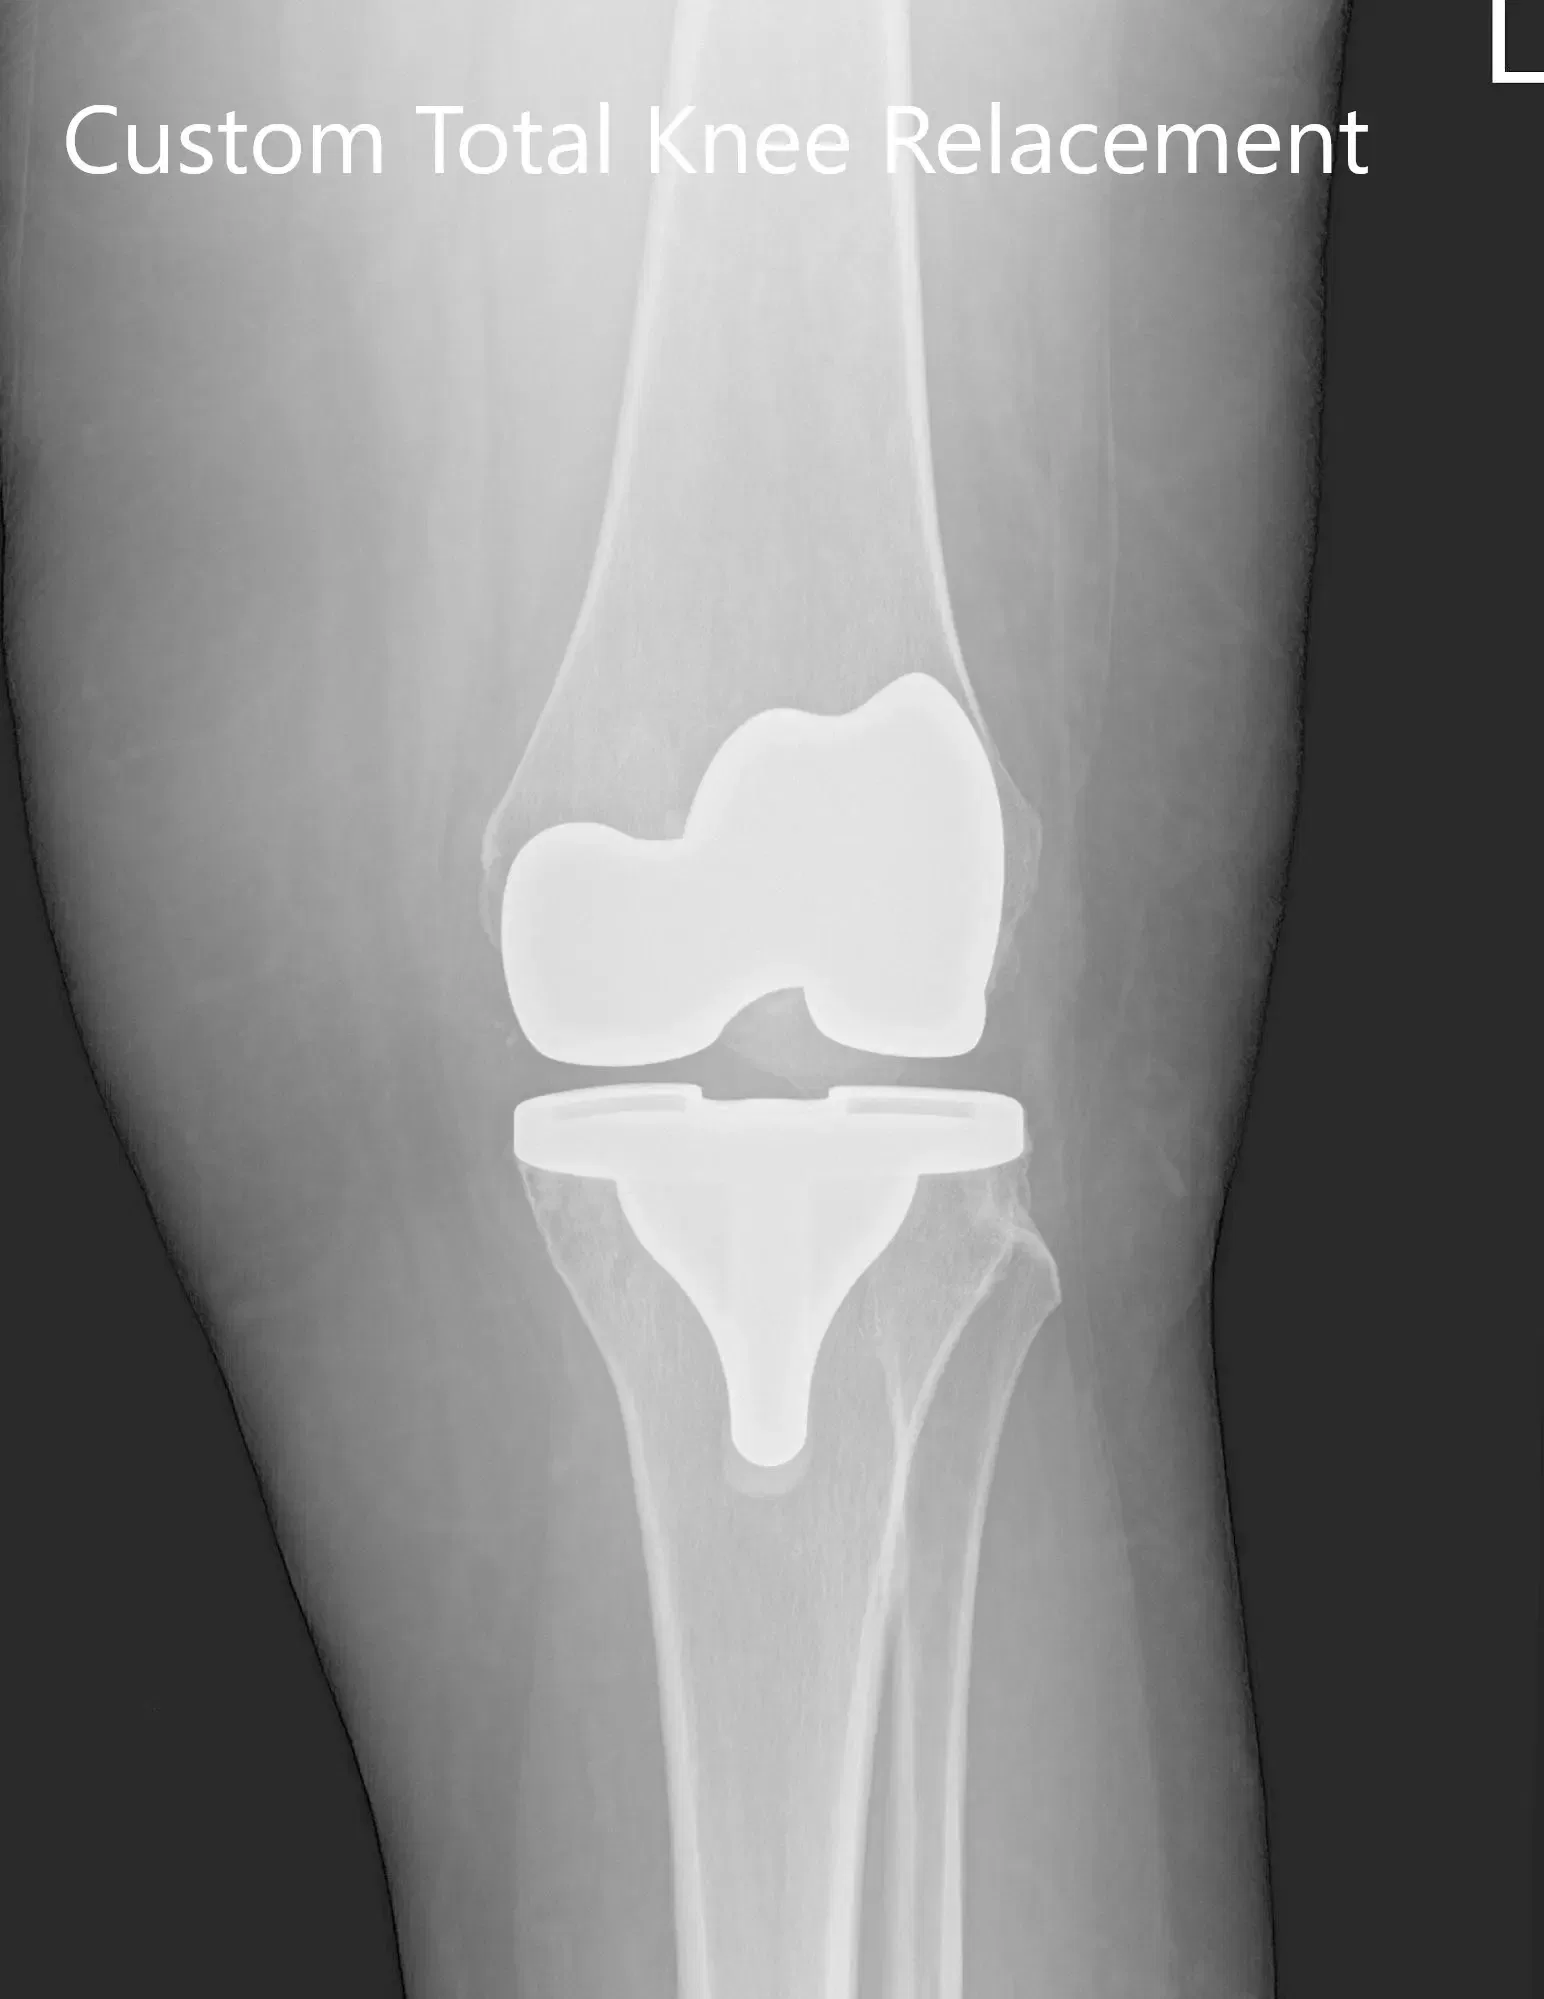

Tres meses de radiografía postoperatoria de la rodilla izquierda que mostró AP e imágenes laterales.

Implante utilizado: Fémur personalizado con tibia y rótula personalizadas (38 mm x 8,5 mm) con inserto de polietileno de 10 mm.

El paciente se sometió a una artroplastia personalizada de la rodilla izquierda